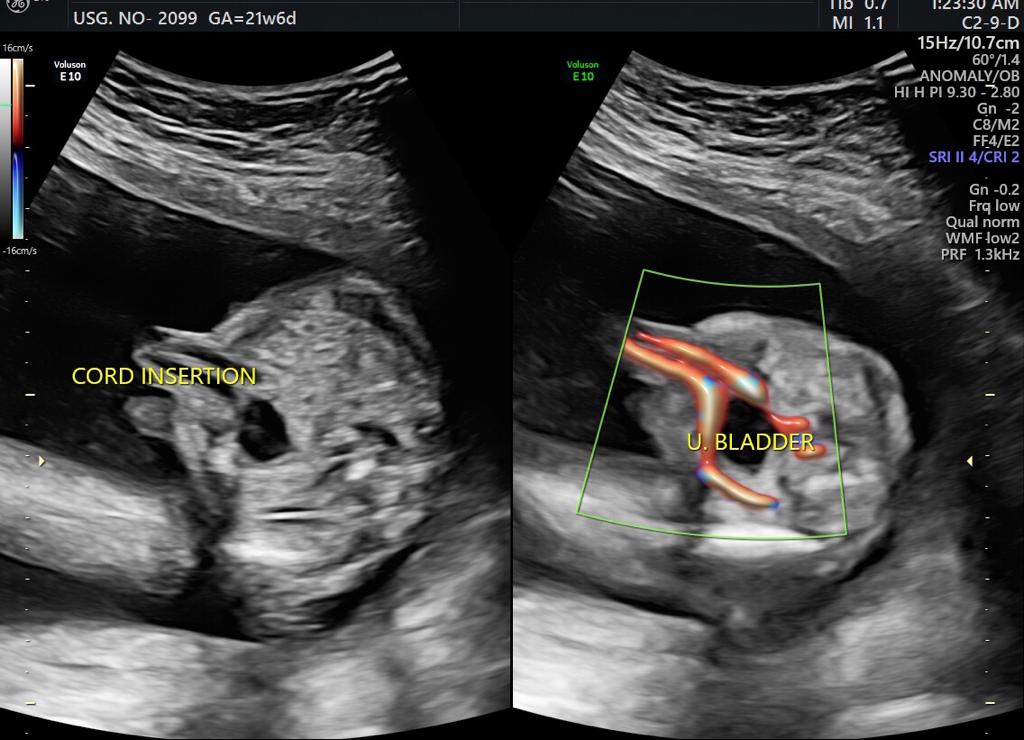

One of the most important scans done during pregnancy is during the second trimester, between weeks 18 and 20. This is called the targeted anomaly scan and is essentially a complete head to toe analysis of the fetus in a clinical perspective. Even though the scan might not be able to identify every single issue, however, gynaecology specialists in Guntur use this scan to validate and rule out any discrepancies with respect to most of the major organs in the Childs body including the brain, kidneys, bones, heart as well as the spinal cord and face, etc. The measurements with respect to every organ are taken also another important aspect of this scan is to identify how the placenta is placed and if it is tending towards creating an issue later on. Visit ultra sound test centers in Guntur at fertility hospitals.

• Organs status: This scan is also used to check if all the organs are formed properly.

Sometimes improper growth could be a cause of concern and on the other side, there are certain disorders which are identified in this scan, some could be rare congenital heart anomalies related to fetalbrain,face, thorax,heart,GIT,renal, skeletal etc